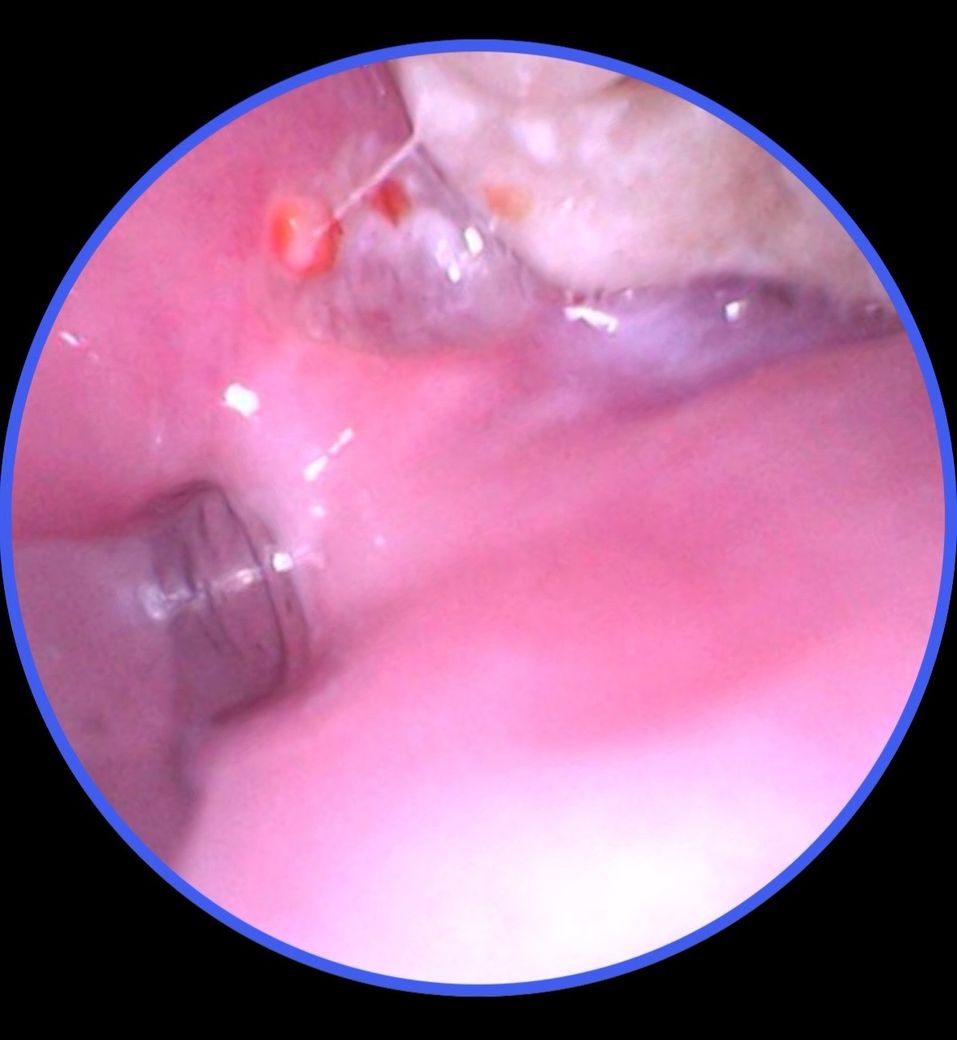

윗 사랑니 뒤쪽에 빨간게 나고 주변이 하얗게 됐습니다.

통증이 있고 특히 뭐 먹을 때나 입을 크게 벌리면 눌리면서 많이 아픕니다. 구내염은 보통 하얀색인데 이건 보니까 빨갛게 올라왔고 주변이 하얗게 됐습니다.

• 1번 째 사진